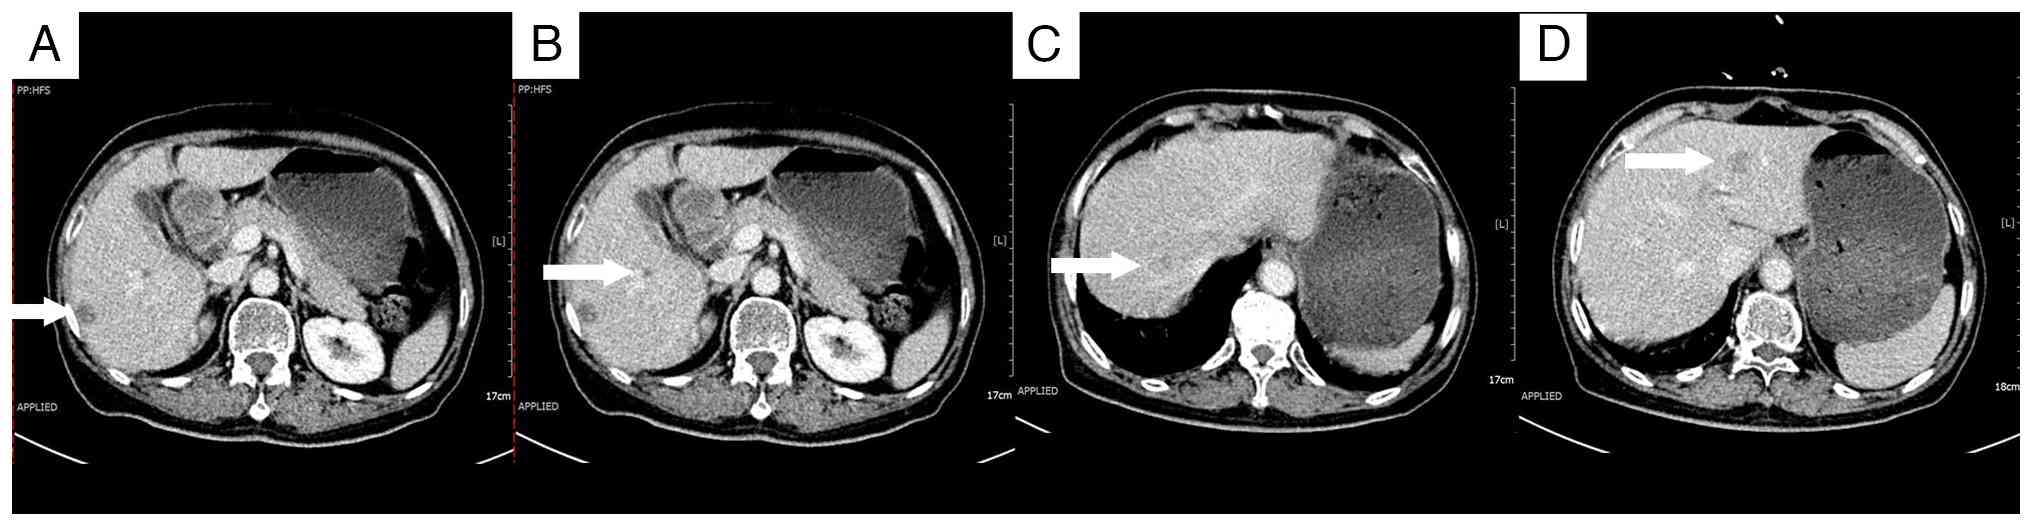

Enhanced computed tomography scans 3

months after surgery. (A) A 14×11-mm lesion beneath the liver

capsule in the right lobe (arrow). (B) An 8×7-mm lesion adjacent to

the right portal vein (arrow). (C) A 17×14-mm lesion at the apex of

the right lobe (arrow). (D) A 15×15-mm lesion in the left lobe

(arrow).

Figure 2.

Enhanced computed tomography scans 3 months after surgery. (A) A 14×11-mm lesion beneath the liver capsule in the right lobe (arrow). (B) An 8×7-mm lesion adjacent to the right portal vein (arrow). (C) A 17×14-mm lesion at the apex of the right lobe (arrow). (D) A 15×15-mm lesion in the left lobe (arrow).

As a standard approach for multiple small lesions, systemic chemotherapy was initiated 3 months after surgery, using the FOLFOX regimen (100 mg oxaliplatin by intravenous infusion on day 1; 200 mg calcium folinate by intravenous infusion on days 1–2; 500 mg fluorouracil by intravenous bolus on day 1, followed by 1,500 mg via continuous intravenous infusion over 44 h). However, the treatment was discontinued due to poor patient tolerance. A multidisciplinary consultation then recommended the use of RFA. However, the pre-procedural assessment identified the following notable challenges for RFA: The lesion beneath the liver capsule in the right lobe of the liver was relatively superficial, which could potentially lead to incomplete coverage by the radiofrequency probe and impact treatment efficacy; the lesion adjacent to the right portal vein posed a heightened risk for RFA due to its proximity to major blood vessels; and the lesion at the apex of the right lobe was too deep for adequate radiofrequency coverage.